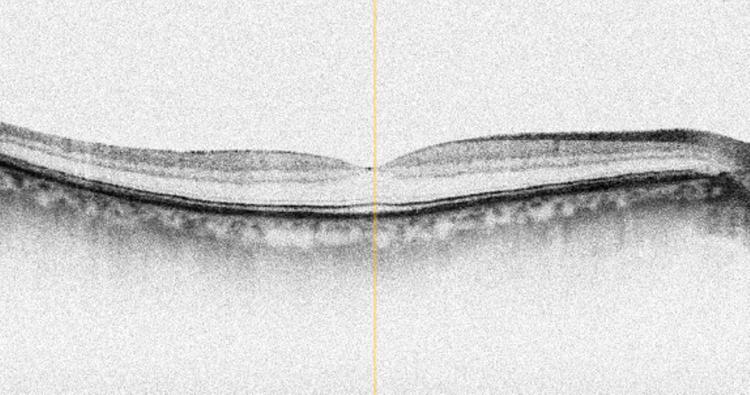

Das Coverbild der November-Ausgabe von OCL: ein OCT einer Makula